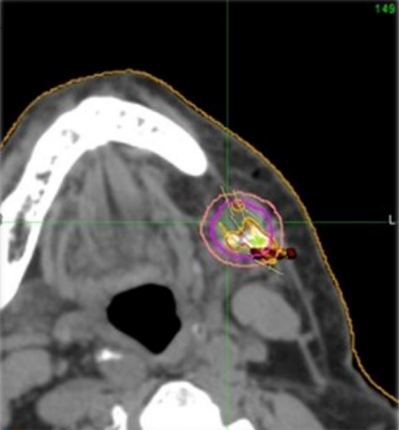

Alpha DaRT enables high-precision alpha radiation for solid #cancer. Radium-224-based alpha #radiotherapy kills the #tumor while sparing healthy tissue #radonc

Most still blast radiation at tumors. What if we fight from within? Alpha DaRT® delivers ultra-high dose inside the tumor - in 1 session, sparing healthy tissue.🎙️Prof. Popovtzer at #IAOO2025 📅 July 18 | 14:00 #AlphaDaRT #Radium224 #OralCancer

What if we fight from within? Alpha DaRT® delivers ultra-high dose inside the tumor - in 1 session, sparing healthy tissue.🎙️Prof. Popovtzer at #IAOO2025